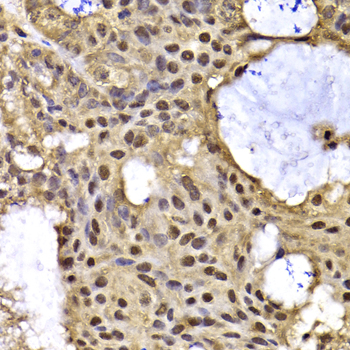

Immunohistochemistry of paraffin-embedded human oophoroma using ARID3A antibody at dilution of 1:100 (x40 lens).